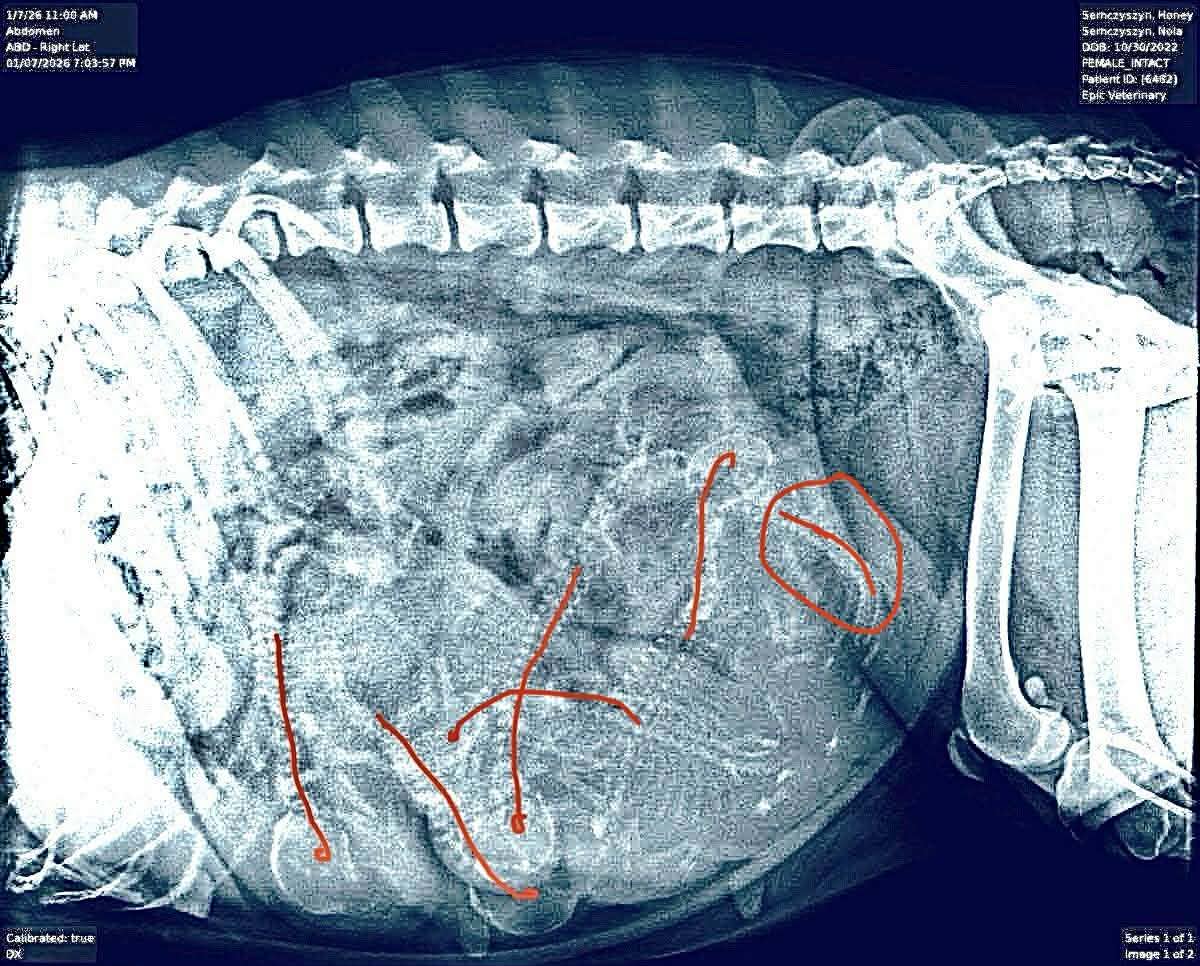

Update: 10 January 2026. Six puppies confirmed on X-Ray. We will be welcoming a new batch of Snarfs early next week.